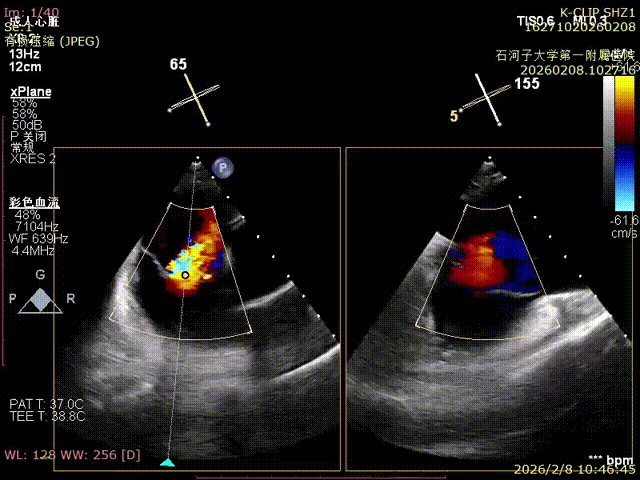

Echocardiographic Findings:Severe tricuspid regurgitation (4+; average vena contracta width, 12 mm). The regurgitation was predominantly anteroseptal and central, with a small posteroseptal component. During systole, the anterior and septal leaflets protruded slightly into the right atrium, with a protrusion height of 2.6 mm. A 6 mm gap was observed at the anteroseptal and central regions. Tricuspid annular dilatation was present (mean annular diameter, 40 mm), with a prominent gap at the anteroseptal region.

Preoperative anteroseptal regurgitation

Preoperative

Preoperative reflux